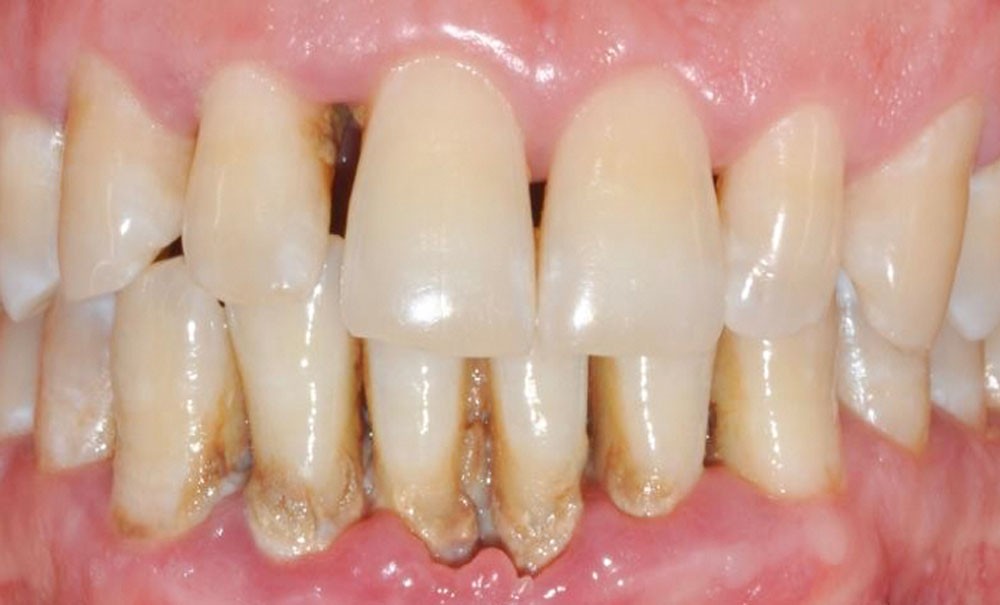

La parodontite est une maladie inflammatoire chronique déclenchée par l’accumulation de biofilm ; elle est d’étiologie multifactorielle [1]. Les manifestations cliniques incluent la présence de poches parodontales, des saignements au sondage, une perte osseuse radiographique verticale et horizontale, et une mobilité dentaire. Si la parodontite n’est pas traitée, elle peut entraîner la perte des dents, bien qu’elle soit évitable et traitable dans la plupart des cas.